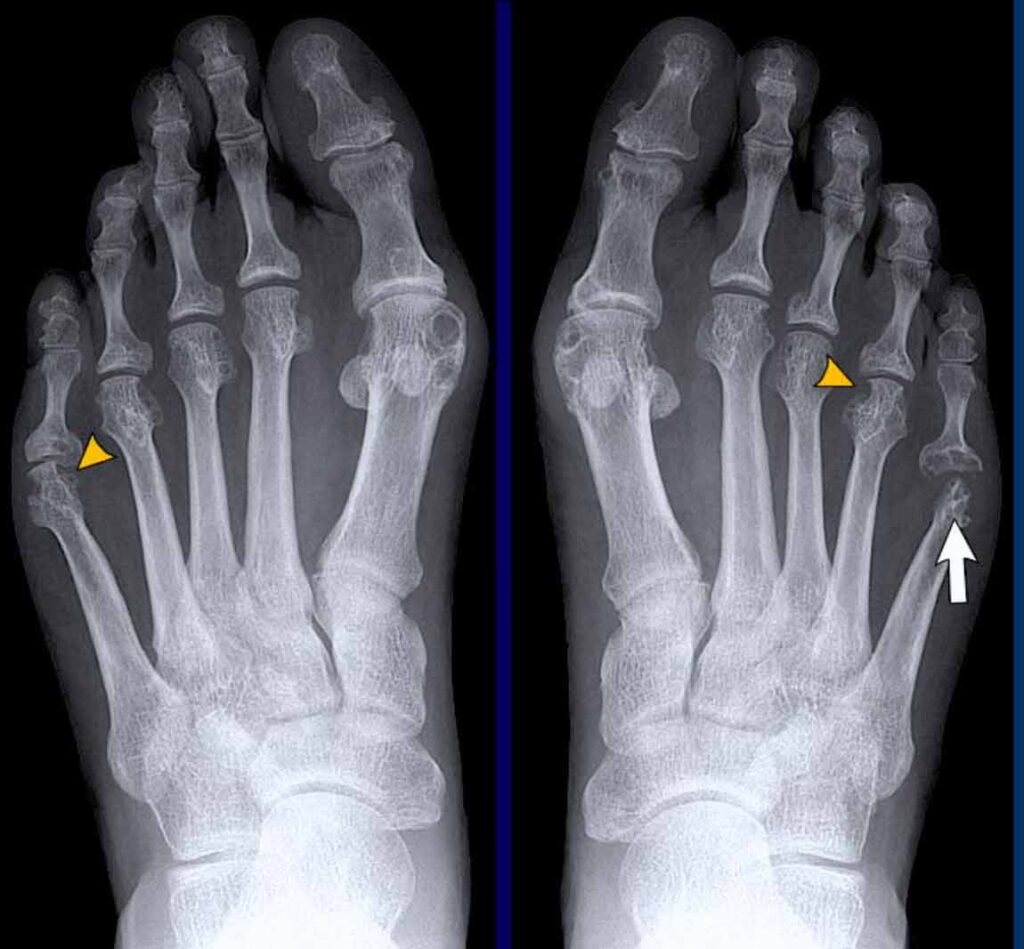

Marginale Erosioner: Sygdommens Kendetegn

Det mest afgørende tegn på leddegigt er tilstedeværelsen af erosioner. Dette er små “gnavery” eller defekter i knoglens overflade, som typisk opstår ved kanten af leddet. Disse områder kaldes de 'nøgne områder' (bare areas), fordi de ligger inden for ledkapslen, men ikke er dækket af beskyttende brusk. Her kan den betændte ledhinde, kendt som pannus, direkte angribe og nedbryde knoglen. Mekanismen menes at være en kombination af direkte mekanisk tryk fra den fortykkede ledhinde og frigivelsen af enzymer og andre stoffer, der stimulerer knoglenedbrydning. Erosionerne starter ofte småt, men kan vokse og føre til betydelig ledskade over tid.